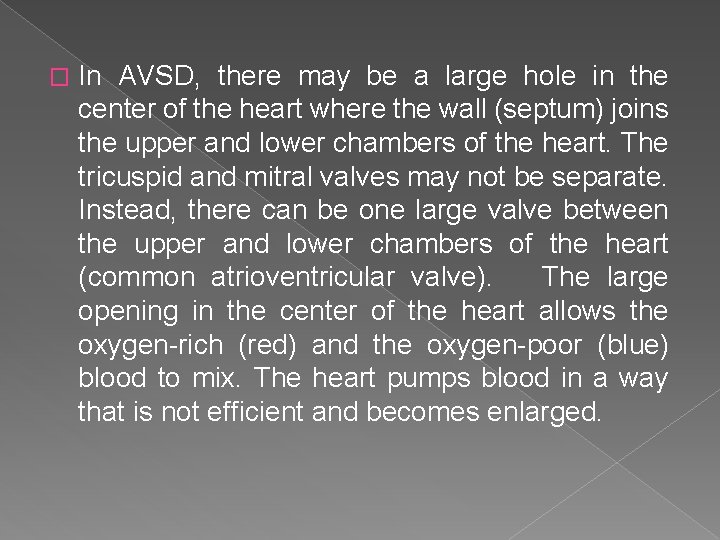

� In AVSD, there may be a large hole in the center of the heart where the wall (septum) joins the upper and lower chambers of the heart. The tricuspid and mitral valves may not be separate. Instead, there can be one large valve between the upper and lower chambers of the heart (common atrioventricular valve). The large opening in the center of the heart allows the oxygen-rich (red) and the oxygen-poor (blue) blood to mix. The heart pumps blood in a way that is not efficient and becomes enlarged.